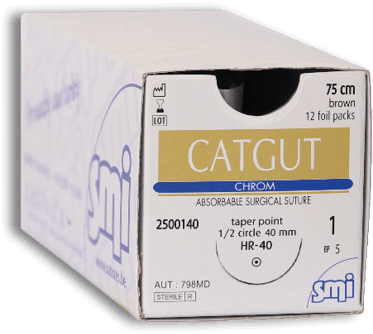

SMI Catgut Chrom Brown Suture

SMI Catgut Chrom Brown Suture